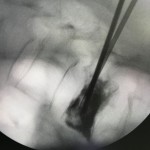

Bác sĩ sẽ sử dụng bóng bơm làm cho thân đốt sống phồng lên sau đó bơm xi măng vào thân đốt sống của bệnh nhân. Xi măng sinh học bơm vào thân đốt sống có tác dụng gắn lại các chỗ gãy xương siêu nhỏ, vừa làm cho thân đốt sống trở nên ổn định, vững chắc, lấy lại chiều cao đốt sống ban đầu, và tăng sức chịu đựng cho thân đốt sống. Lớp xi măng cứng dần lên chỉ sau 1 giờ, bệnh nhân hầu như hết đau, sau 6 giờ có thể tự ngồi dậy, sau 1 ngày tập đi lại bình thường và sau 3 ngày bệnh nhân được xuất viện.